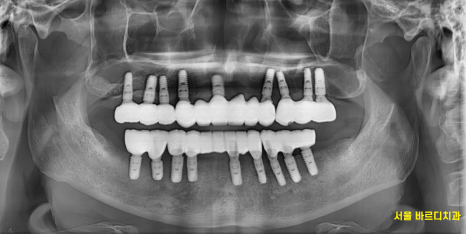

디지털 임플란트 기술을 활용

미리 모형도 제작하여

당일 한번에 위아래 전악 임플란트를 식립하기로 하였습니다.

수술은 하루에 전악이 이루어졌습니다.

231109

미리 네비게이션 기술을 활용하여

수술 식립 각도, 사이즈를 분석했습니다.

잇몸 절개를 꼭 필요한 부위만 진행

출혈, 붓기를 감소시킬 수 있었고

실제 수술 시간은 1시간이 조금 넘어 끝났습니다.

수술 후 골유착이되는 5개월 동안은

임시틀니를 만들어 드렸는데요.

5개월 뒤 2차 수술을 진행했습니다

간단히 말해 골 유착을 위해 잇몸 안에 묻어두었다면

뽄 뜰 준비를 하는 겁니다.

240507

뼈 안에 묻혀있는 임플란트와

잇몸 밖에 나사를 연결하여

기둥 뽄을 먼저 떴습니다.